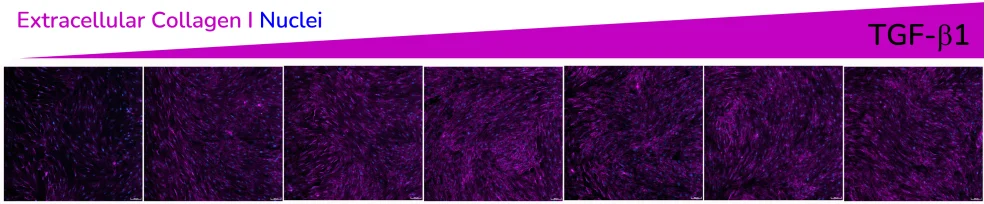

- Increased extracellular collagen I deposition

Extracellular collagen I deposition in response to dose-dependent treatment with TGF-β1. Images were acquired using the ImageXpress Confocal HT.ai imaging system. Image Credit: Newcells Biotech

Exposure to ALK5 inhibitors SB431542 and SB525334 reduces the effect of TGF-β1 at pathophysiologically relevant concentrations.

- The addition of a macromolecular crowder (MMC) agent to the culture medium creates a more in vivo-like environment and encourages the deposition of secreted extracellular collagen I, increasing signal sensitivity